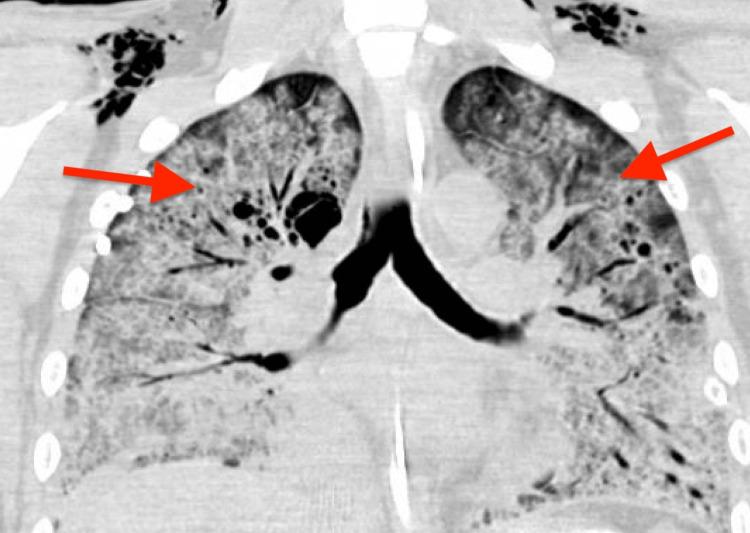

Primary central nervous system lymphoma (PCNSL) exists as an HIV-associated malignancy, with its etiology driven primarily by Epstein-Barr virus (EBV) in the setting of absence of EBV-specific CD4+ T cell function, with CD4 counts averaging <50 cells/microliter. Before the development of antiretroviral therapy (ART), the treatment of HIV-associated PCNSL was primarily whole brain radiation therapy, which was fraught with long-term cognitive dysfunction. The availability of ART made the treatment of HIV-associated PCNSL possible to treat with curative intent. Here, we discuss a complex case of HIV-associated PCNSCL in a young male patient, wherein immune reconstitution combined with lymphoma-directed systemic therapy was ineffective in eradicating malignancy.